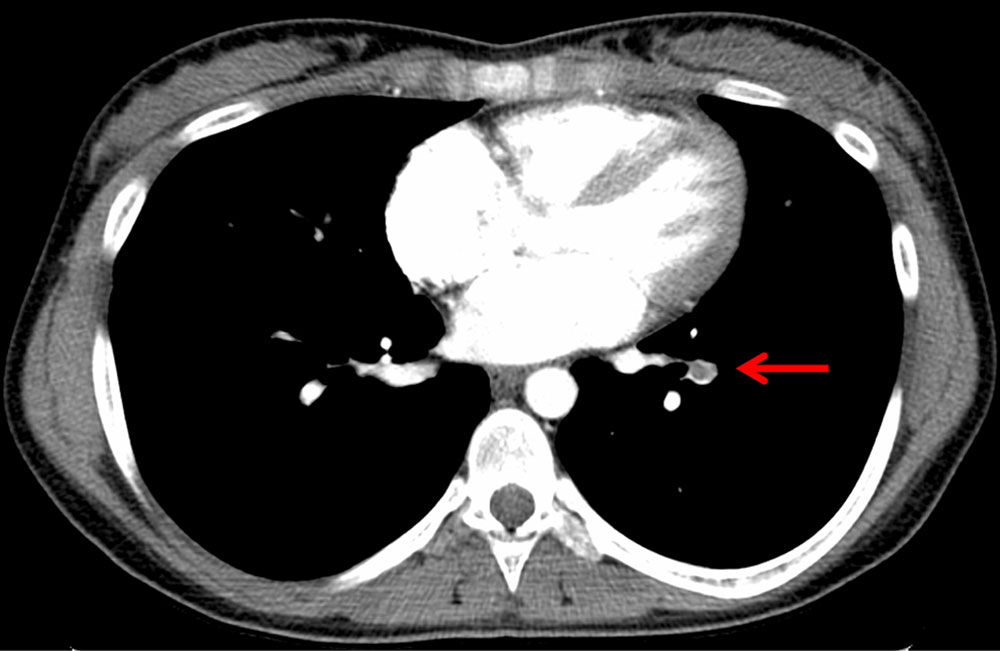

Weitaus häufiger sind kongenitale arteriovenöse Fisteln mit der hereditären hämorrhagischen Teleangiektasie vergesellschaftet, auch als Morbus Osler bekannt. Je nach zugrundeliegender Störung können bei bis zu 75 % der Betroffenen Fast-flow-Shunts zwischen Pulmonalarterie und Pulmonalvene diagnostiziert werden. Daraus können sich ein intrapulmonaler Rechts-Links-Shunt mit zerebralen paradoxen Embolien, Dyspnoe, Zyanose und Trommelschlegelfinger bis hin zur chronischen kardiopulmonalen Insuffizienz entwickeln.